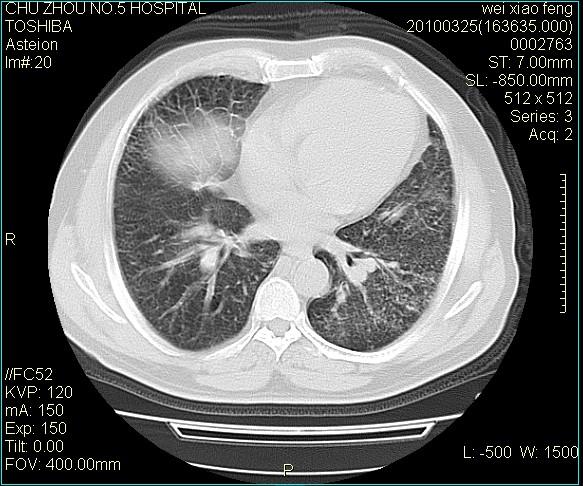

男,60岁,反复咳、痰、喘3月,加重3天。

双肺间质性改变。

考虑双肺血型潘散肺结核/

间质性肺炎伴间质纤维化!不排除伴有职业病!

双肺间质纤维化,双肺血型潘散肺结核。

考虑间质性肺炎伴间质纤维化。

右肺中叶结节影为原发灶,考虑右肺中叶周围型肺癌并淋巴道转移